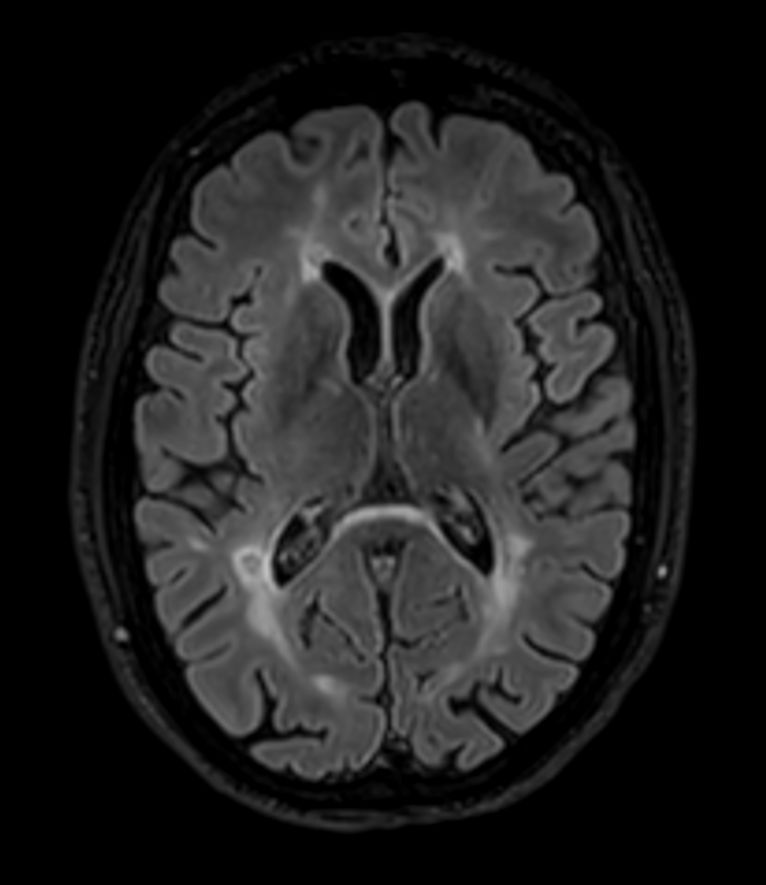

3D T2w FLAIR BrainVIEW Compressed SENSE

3D T2w FLAIR BrainVIEW (reformat) Compressed SENSE